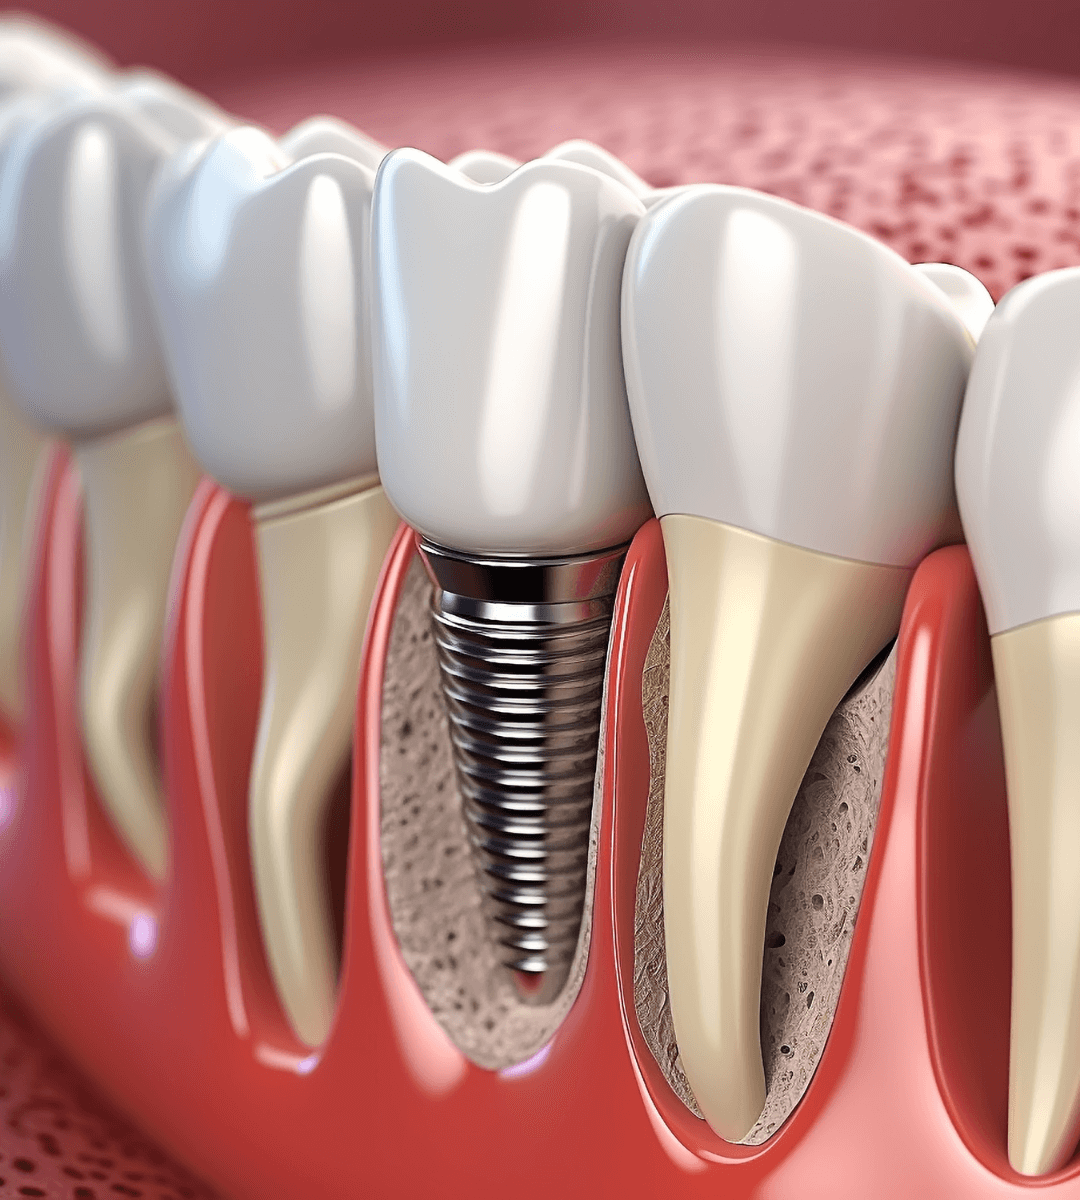

Tradicionalmente, el proceso de implantes dentales requería de dos etapas separadas por varios meses:

- Primero se colocaba el tornillo (implante) y se esperaba a que se integrara en el hueso

- Meses después se colocaba el diente (corona).

La Carga Inmediata revoluciona este protocolo. Consiste en colocar una prótesis fija provisional sobre los implantes en el mismo día de la cirugía (o en las 24-48 horas siguientes).

1. Estudio 3D: Realizamos un escáner (TAC) de tu mandíbula para ver la calidad de tu hueso.

2. Cirugía Guiada: Planificamos la posición exacta del implante por ordenador. Esto nos permite ser mínimamente invasivos.